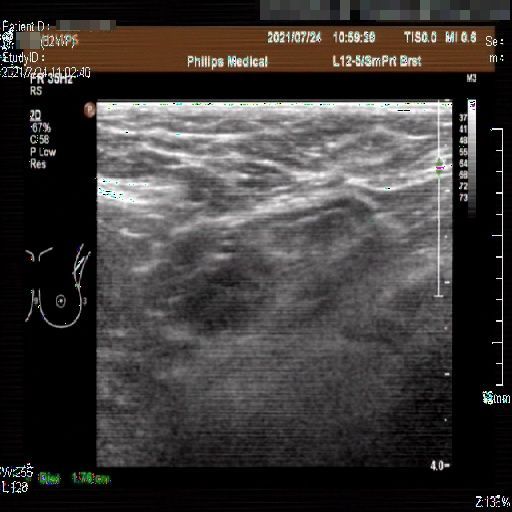

Images with certain annotations are considered noisy images in the context of the noise removal task, and corresponding images without these annotations are considered clean. Some typical images with various annotation are provided in Fig. 1.

In essence, a body marker annotation is a marker selected from a fixed set of icons that indicates different regions of the human body and its current orientation. It is typically located at the edge of the ultrasnoic image area and is labeled by the sonographer. On some ultrasound machines, the body marker annotation has a fixed position.

(a)

Figure 1: Images with various annotations. (a) body marker annotation, (b) radical line annotation, (c) vascular flow annotation.